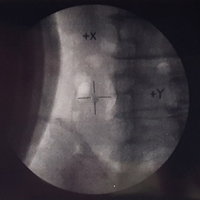

治療前にまず腹部単純X線撮影を行い、治療当日の腎結石の場所・大きさ等を把握します。そのうえでX線透視装置を用いて、結石に衝撃波の照準を合わせていきます。治療中は泌尿器科医と共に常に患者様の様子を観察し安全に治療が行えているか確認しています。治療後にもう一度腹部単純X線撮影を行い、腎結石の形状変化等を確認します。一回で治療が終了することもありますが、場合によっては数回にわたることもあります。